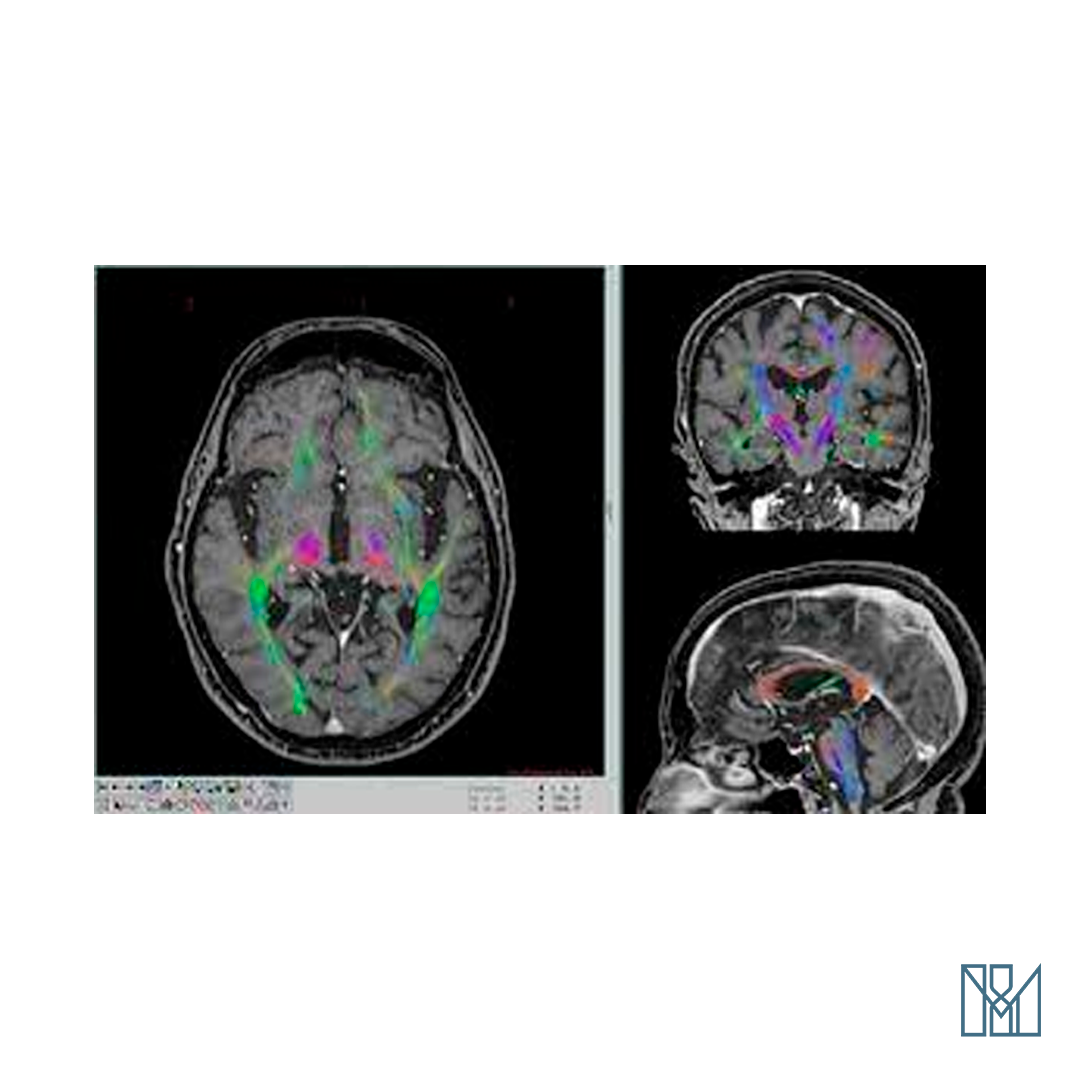

Sistema para planejamento de procedimentos estereotáxicos, neurocirurgia funcional, braquiterapia estereotáxica e fusão multimodal de imagens. Possui versões para os principais marcos estereotáxicos disponíveis no mercado, com reconhecimento automático dos fiducial markers. Permite realizar a fusão multimodal de imagens para CT, MRI e PET com Maximização da Informação Mútua e a fusão com diversos atlas estereotáxicos funcionais.

O programa MNPS é o resultado de mais de 20 anos de desenvolvimento de técnicas de planejamento para procedimentos estereotáxicos baseado em computadores pessoais e neuroimagens e tem suporte para os principais marcos estereotáxicos disponíveis no mercado.